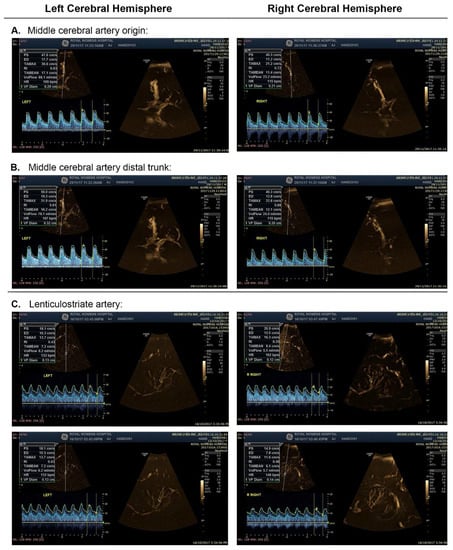

2.4. Procedure